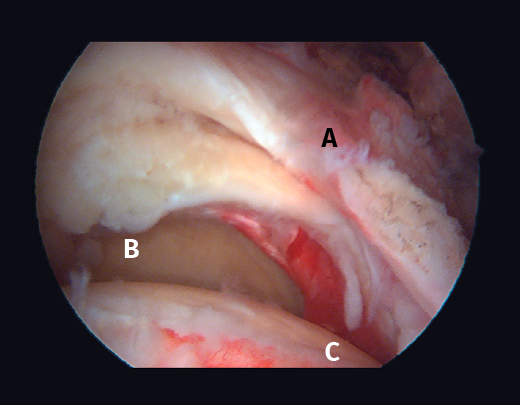

Figura 2. Rotura del manguito rotador en forma de U. A: tendón infraespinoso; B: tendón supraespinoso; C: cabeza humeral.

Figura 5. Rotura de tipo C1. A: rotura pequeña de espesor completo del supraespinoso; B: cabeza humeral.